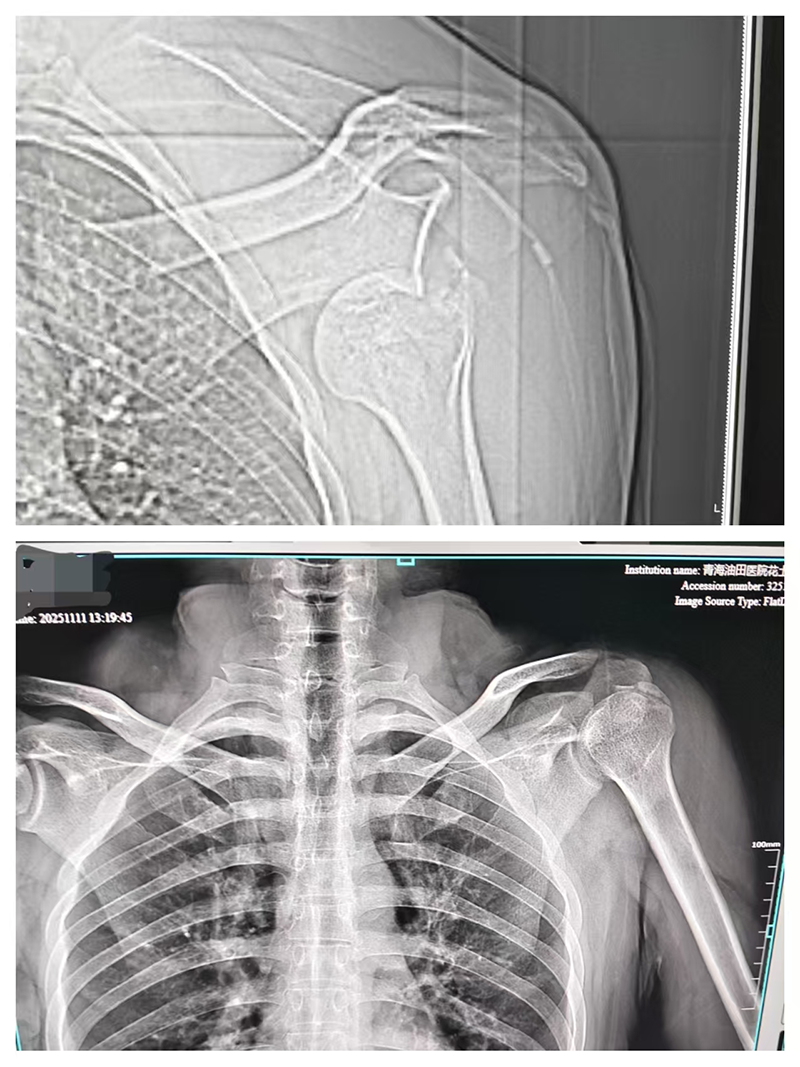

患者抵达分院时,面色苍白、表情痛苦,左肩关节无法自主活动。分院医护团队第一时间启动紧急救治流程,快速为患者测量生命体征,并完善胸部CT左肩关节X线、CT及三维重建等相关检查。经过完善的检查,患者确诊为左肩关节脱位,左侧肱骨大结节撕脱性骨折、肺挫伤,若不及时处理,可能导致关节功能受损加重、肺部损伤恶化等严重后果。

经过对症治疗后,患者生命体征平稳,左肩关节肿胀逐渐消退,疼痛症状明显缓解,未出现病情加重迹象。考虑到患者存在肱骨大结节撕脱性骨折可能伴有肩袖损伤,需进一步接受专科系统治疗,患者要求转往上级医院进一步治疗医务人员协助患者转院,并安排救护车护送送患者安全转诊,确保治疗的连续性与安全性。